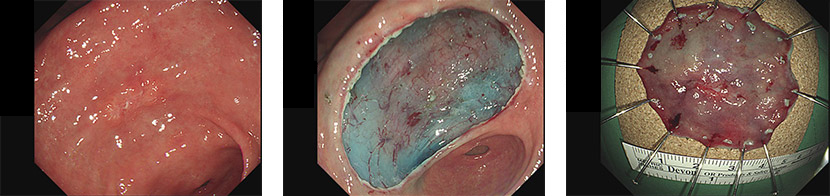

ESD(内视镜粘膜下切除术)) 是指摘除内窥镜下胃癌或大肠癌病变部位的手术。

1. 胃

1) 不局限于黏膜的2cm以下分化型早期癌

2) 1.5cm以上的腺瘤、异形性症

3) 伴随纤维化的腺瘤

4) 粘膜下肿瘤